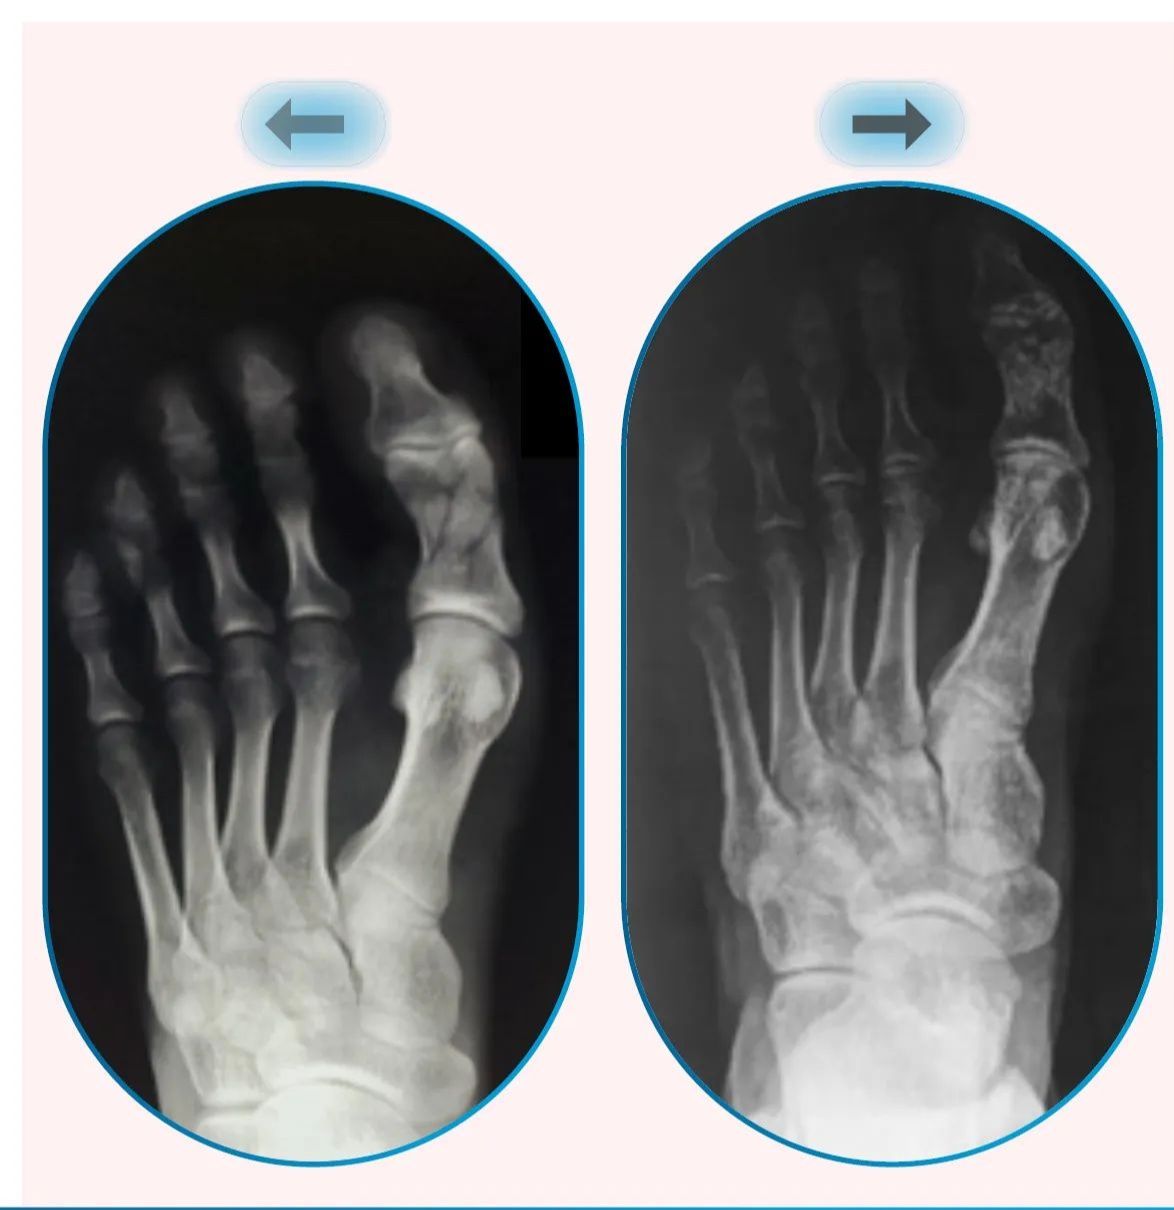

【骨折復原卡關?關鍵在刺激對了沒】

一位 42 歲來自秘魯排球選手的腳拇趾骨折,

做了 20 次傳統治療仍無進展。

從來到駿品治療16次後,

僅數週——

X 光骨癒合明顯提升

無疼痛

可正常負重、行走